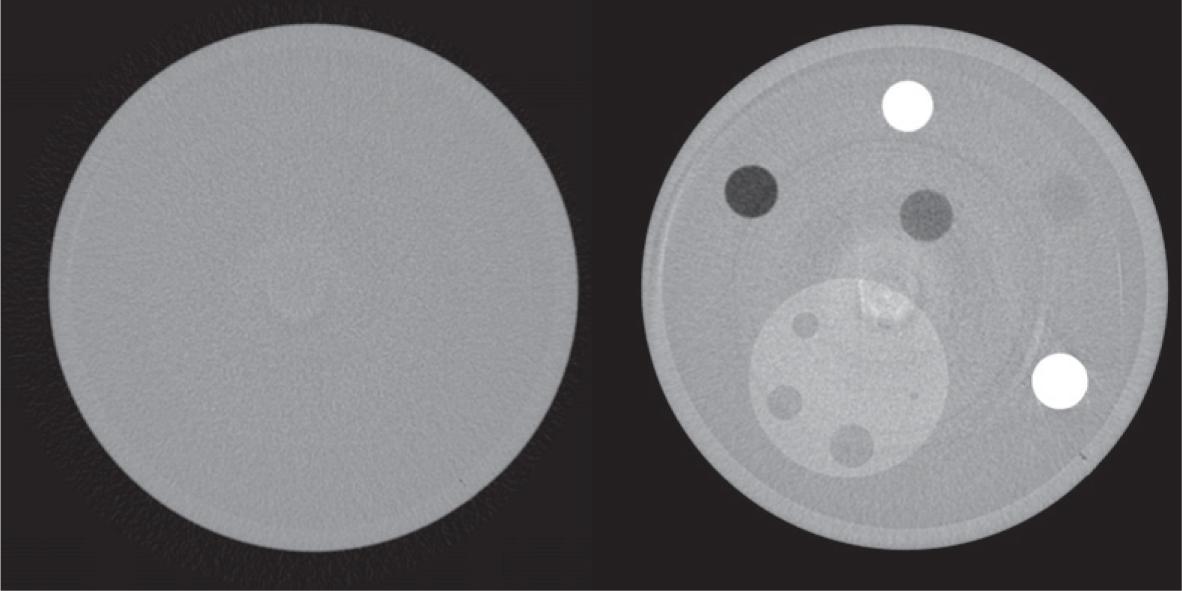

Figure 2